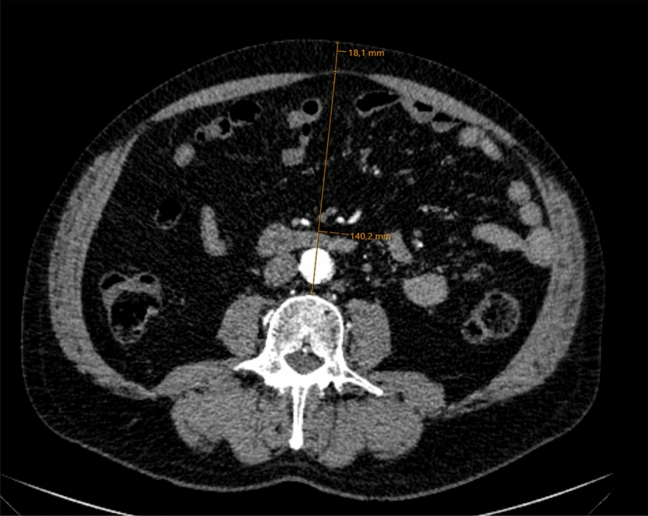

The fat tissue parameters were measured in one axial CT slice at the level of the L3 vertebra, as at this level mostly mesenteric fat is depicted on CT slices and no colonic distension would influence the measurements. Visceral obesity (VO) was determined from the ventral aspect of the vertebra to the rectus sheath in the anterior–posterior direction (AP). Subcutaneous obesity (SCO) was represented by the distance between rectus sheath and skin level. Figure 1 shows an example of the typical measurement. Combined Obesity (CBO) was the addition of both distances. Additionally, the ratio between both values was calculated (visceral to subcutaneous ratio = VSR) in order to generate an expression for fat tissue distribution and in response to Kim et al.8.

Figure 1.

Contrast enhanced CT scan showing the measurement (orange line) of the visceral obesity from the ventral L3 vertebra to the linea alba and subcutaneous obesity from the linea alba to the skin.